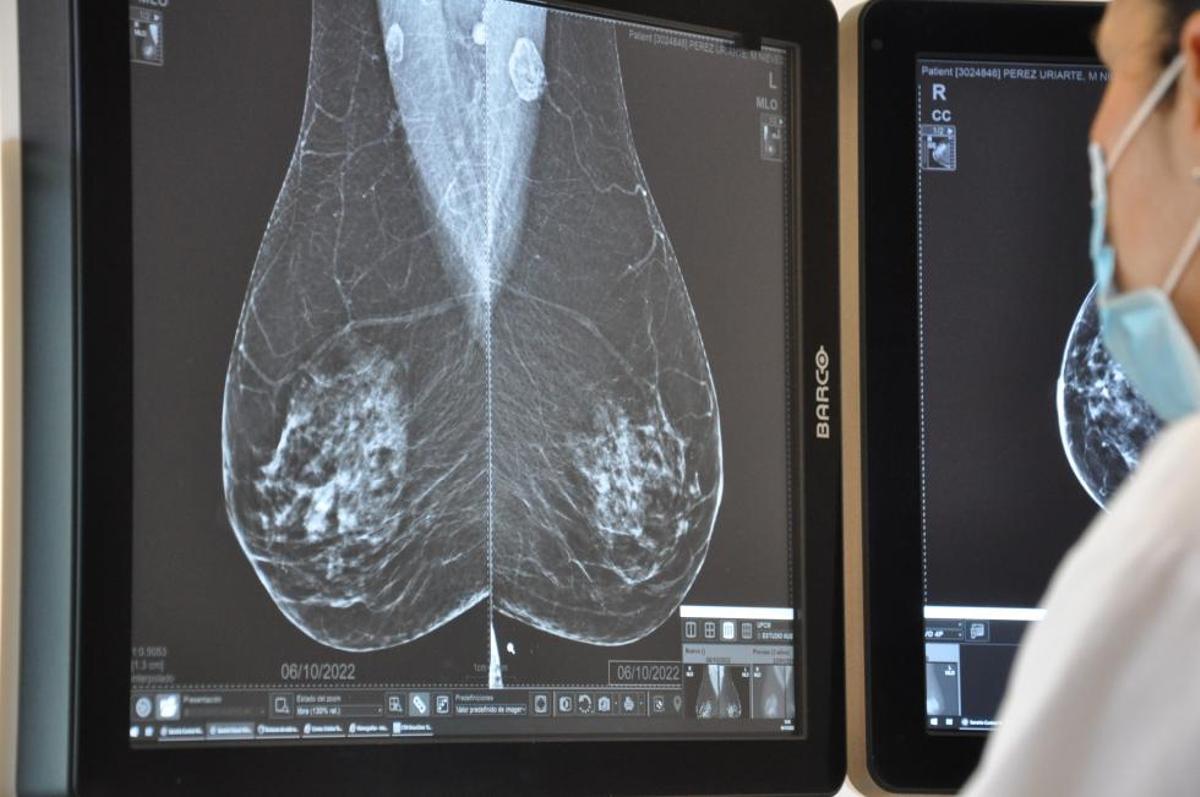

Una mujer se somete a una mamografía en un centro médico de Benidorm. / J.HERNÁNDEZ

Las mujeres valencianas podrán recibir toda la información relacionada con las mamografías del cribado de cáncer de mama -citas y resultados- por mensaje de texto o correo electrónico, entre otras fórmulas tecnológicas, a partir del año 2026, aunque si lo prefieren podrán seguir utilizando el método actual: por carta ordinaria. Así lo explican fuentes oficiales de la Conselleria de Sanidad, las cuales detallan que este cambio supondrá "una mejora sustancial del modelo de invitación" con el que esperan "un incremento en la participación". Pero, sobre todo, supondrá ofrecer una "comunicación más rápida y efectiva de los resultados", con lo que se podrían evitar los problemas detectados en Andalucía, donde más de 2.000 mujeres, según los datos de la Junta, se han visto afectadas por un retraso de hasta dos años de los resultados sospechosos de sus mamografías.

El cambio en la comunicación con las mujeres supone, según el departamento de Marciano Gómez, encarar la última fase de su plan de impulso para el cribado del cáncer de mama basado en seis ejes -este sería el último de ellos- en el que llevan trabajando desde inicios de legislatura y, sobre todo, desde la demora detectada hace casi dos años. El primero de ellos fue la renovación de casi la mitad de los 24 mamógrafos, el cambio de los 11 citados anteriormente, al detectar que "no estaban en condiciones de uso". El segundo punto fue la introducción de la inteligencia artificial en la lectura de las mamografías, uno de los mantras tanto del conseller Gómez como del president Carlos Mazón, con una precisión del 99 %. Según explican, el 93 % de los resultados coinciden con la valoración del radiólogo o radióloga y, en el largo plazo, permitirá "reducir progresivamente hasta en un 40 % la carga asistencial en las Unidades de Prevención de Cáncer de Mama (UPCM).